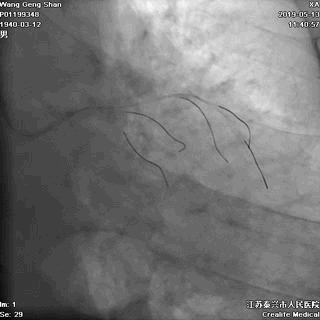

03 第一第二对角支保护

对角支导丝到位

左冠共计5根导丝

前降支近段支架植入后用非顺应性球囊高压扩张